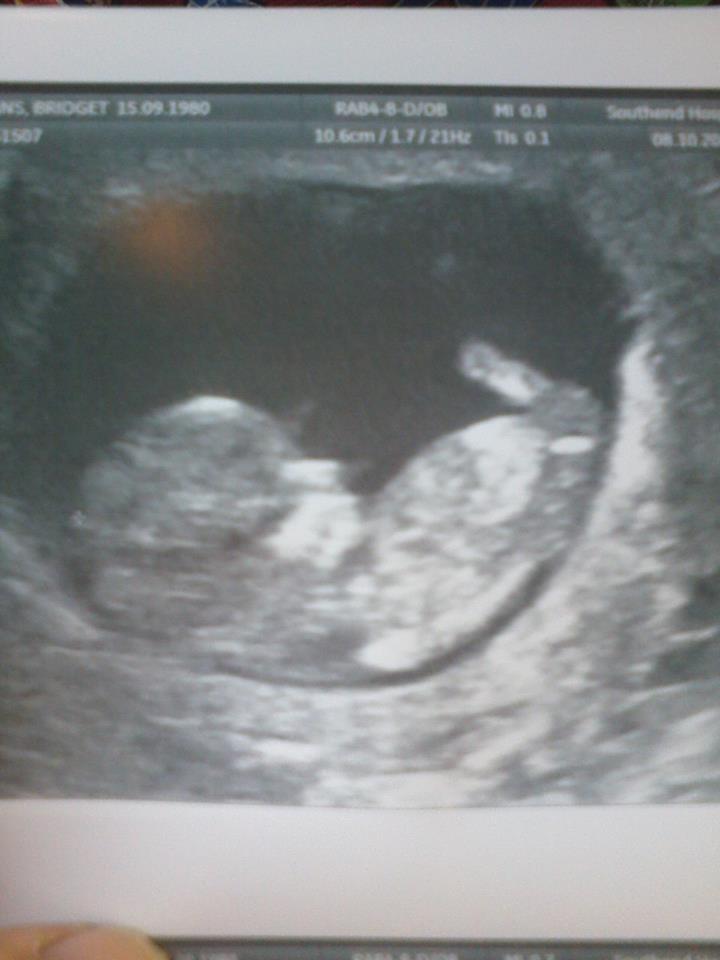

this was my 12 week scan although i was only 11+3 Attachment 22122

There's no nub but that is much too early for any kind of accuracy! 13 weeks is best!

very early but skull looks girlie.

Looks girlie but that's way too early for guesses x

Girly but early

Got a boy feeling about this one:)